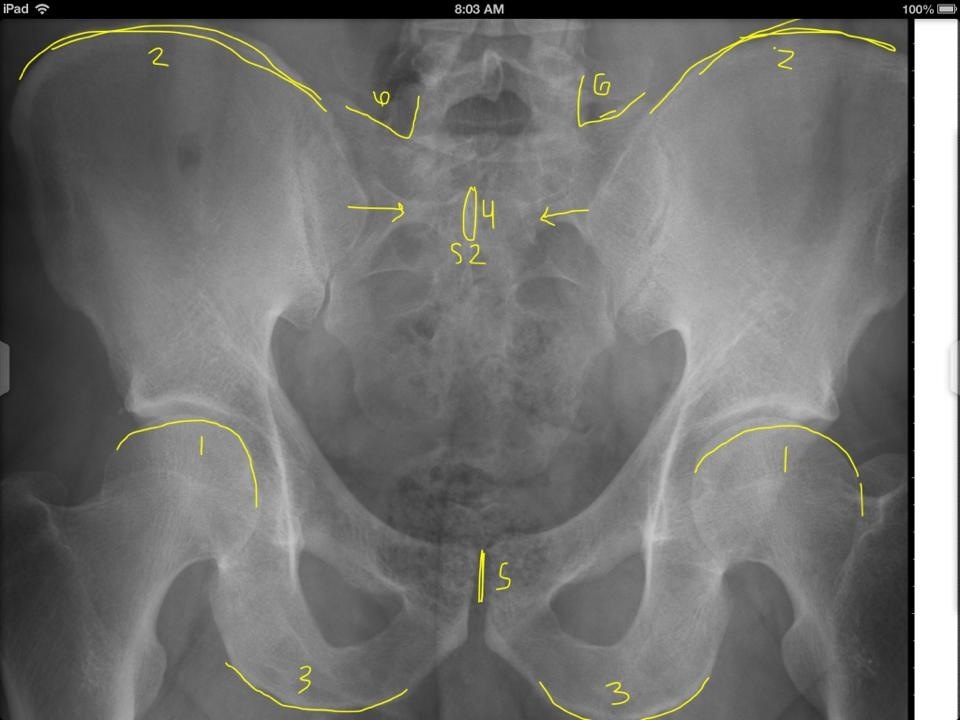

1

Superior aspect of femur heads

2

3

Inferior aspect of ischial tuberosities

4

S2 tubercle

5

Pubic symphysis

6

Sacral Grooves